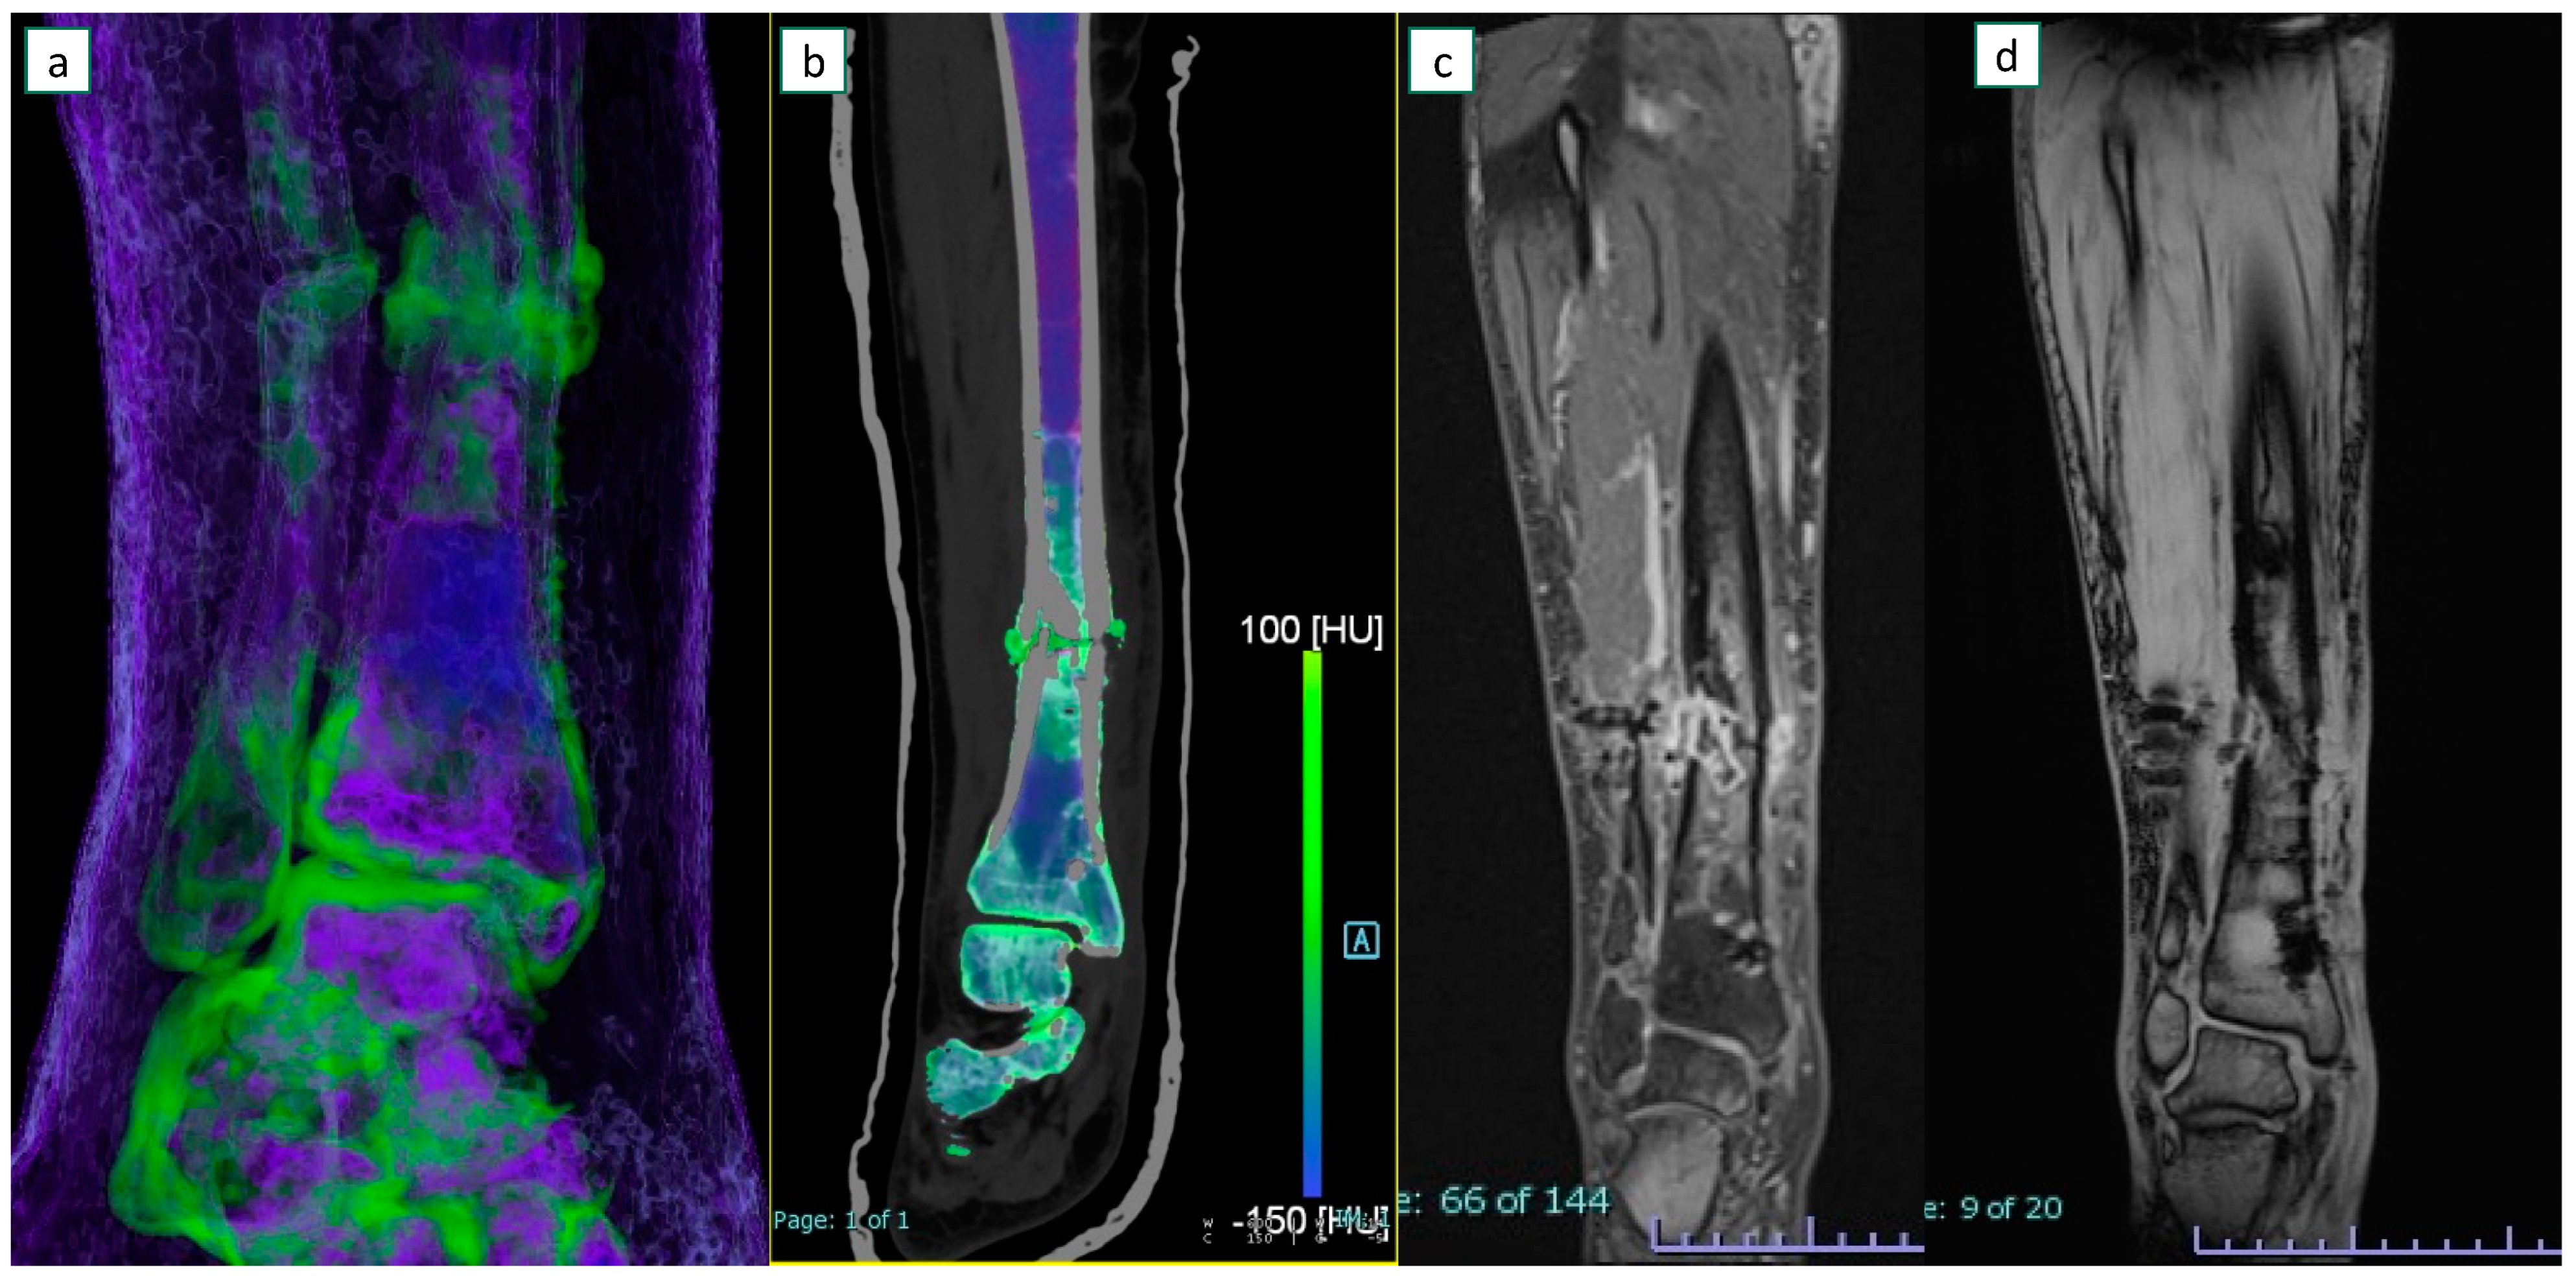

3.3. Imaging Results